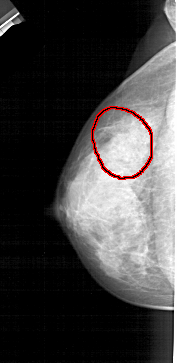

A_1446_1.LEFT_CC

LEFT_CC LINES 4711 PIXELS_PER_LINE 2296 BITS_PER_PIXEL 12 RESOLUTION 43.5 OVERLAY

FILE: A_1446_1.LEFT_CC.OVERLAY

TOTAL_ABNORMALITIES 1

ABNORMALITY 1

LESION_TYPE CALCIFICATION TYPE AMORPHOUS DISTRIBUTION SEGMENTAL

ASSESSMENT 2

SUBTLETY 3

PATHOLOGY BENIGN

TOTAL_OUTLINES 1

BOUNDARY